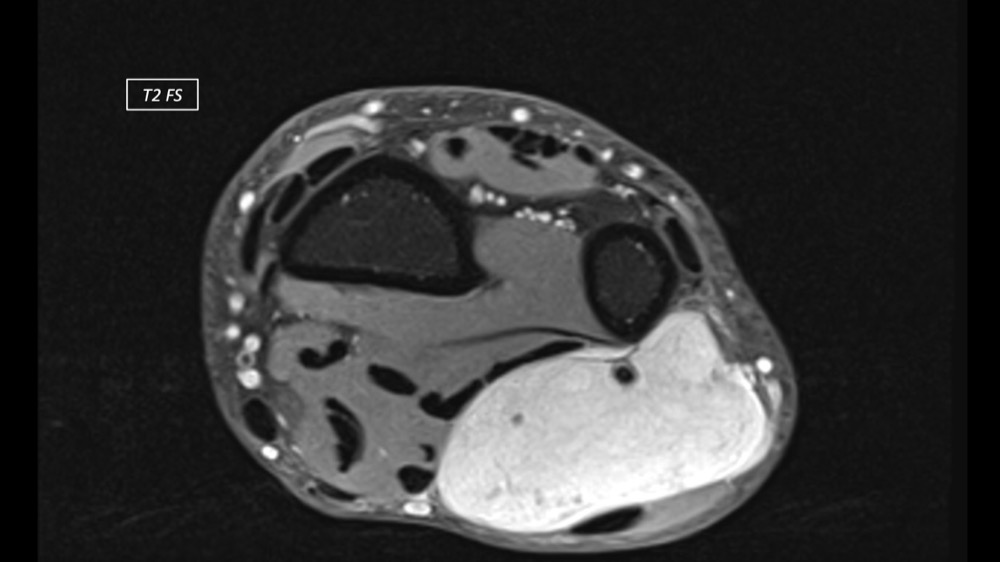

Dupuis / Benoist / Leclerc / Bousson 18/05/2022